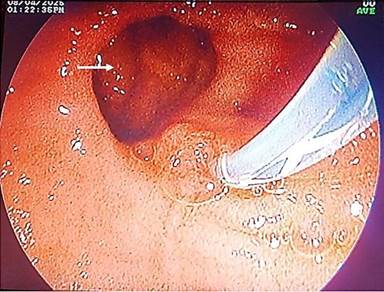

Imagen endoscópica donde se señala con la flecha, divertículo yuxtapapilar posterior a la canulación.

Fuente: imagen de los autores.